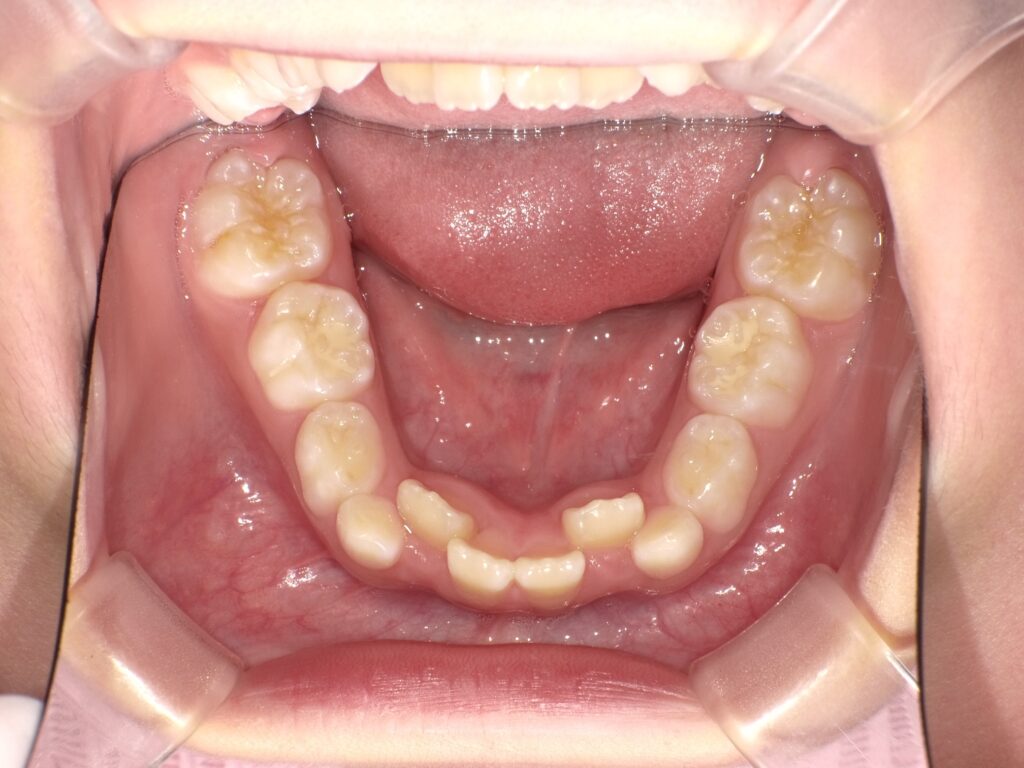

1. 歯並びが乱れている場合

歯並びが悪すぎて、食べ物を噛みにくかったり、発音に支障が出ている場合。

また、歯並びが悪いことで虫歯や歯周病が進行しやすくなることもあります。

歯が生える順番や位置が乱れていることで、隣の歯に悪影響を与えたり、食事や会話に支障が出ている場合です。

また、歯が重なり合っていたり、抜ける場所に問題がある場合も、矯正治療が有効です。